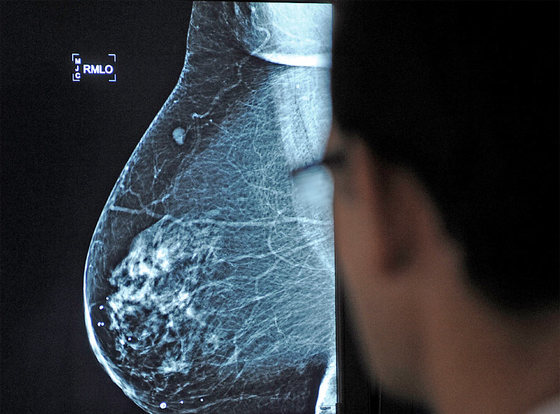

Un médico observa una mamografía / CRISTINA QUICLER

En medicina, más no es siempre mejor

Aún hoy, en España cerca de una cuarta parte de las mujeres no visita al ginecólogo. El 75% sí que acude periódicamente. Muchas, para pasar por mamografías y citologías, ambas pruebas de cribado dirigidas a prevenir el cáncer de mama y de cérvix. Pero tanto el defecto como el exceso pueden acabar perjudicando la salud.